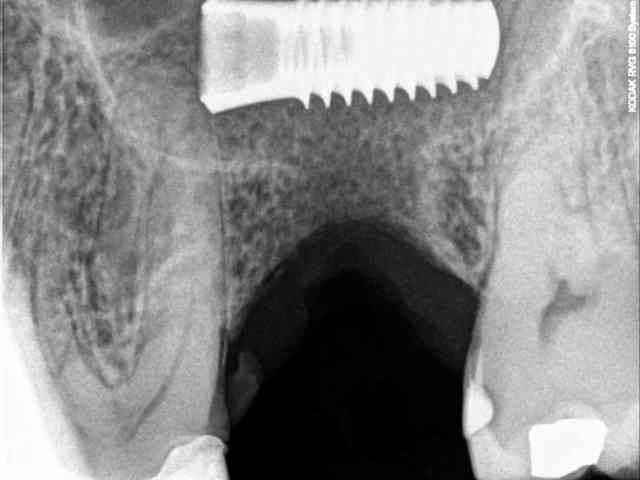

ce matin après avoir reçu un coup de téléphone d'une consœur, j'ai reçu en urgence un patient avec un petit souci...

l'implant a été posé en aout, apparemment dans une zone SA3 et apparemment sans utiliser la technique de Summers (d’après le patient , pas de biomat utilisé). je dis apparemment, car on se doit de tout mettre au conditionnel avec les patients.

ce dernier a perdu la vis de cica peu de temps après la pose et a mis plusieurs semaines pour se la faire remettre.

bref, depuis 4 jours il a mal, il consulte et là, c'est le drame...

migration dans le sinus et début d'infection.

je ne suis pas sure toutefois d'être en face d'une CBS dans la mesure où ma le teste de Walsava est négatif, et où l'implant semble accolé au plancher sinusien.

j'espère qu'il est simplement sous la membrane de Schneider, auquel cas il devrait mettre assez facile d'aller le chercher.

pas d'ostéointégration possible car l'implant était dans sa bonne position il y a encore 15 jours !

j'ai oublié ce détail important.